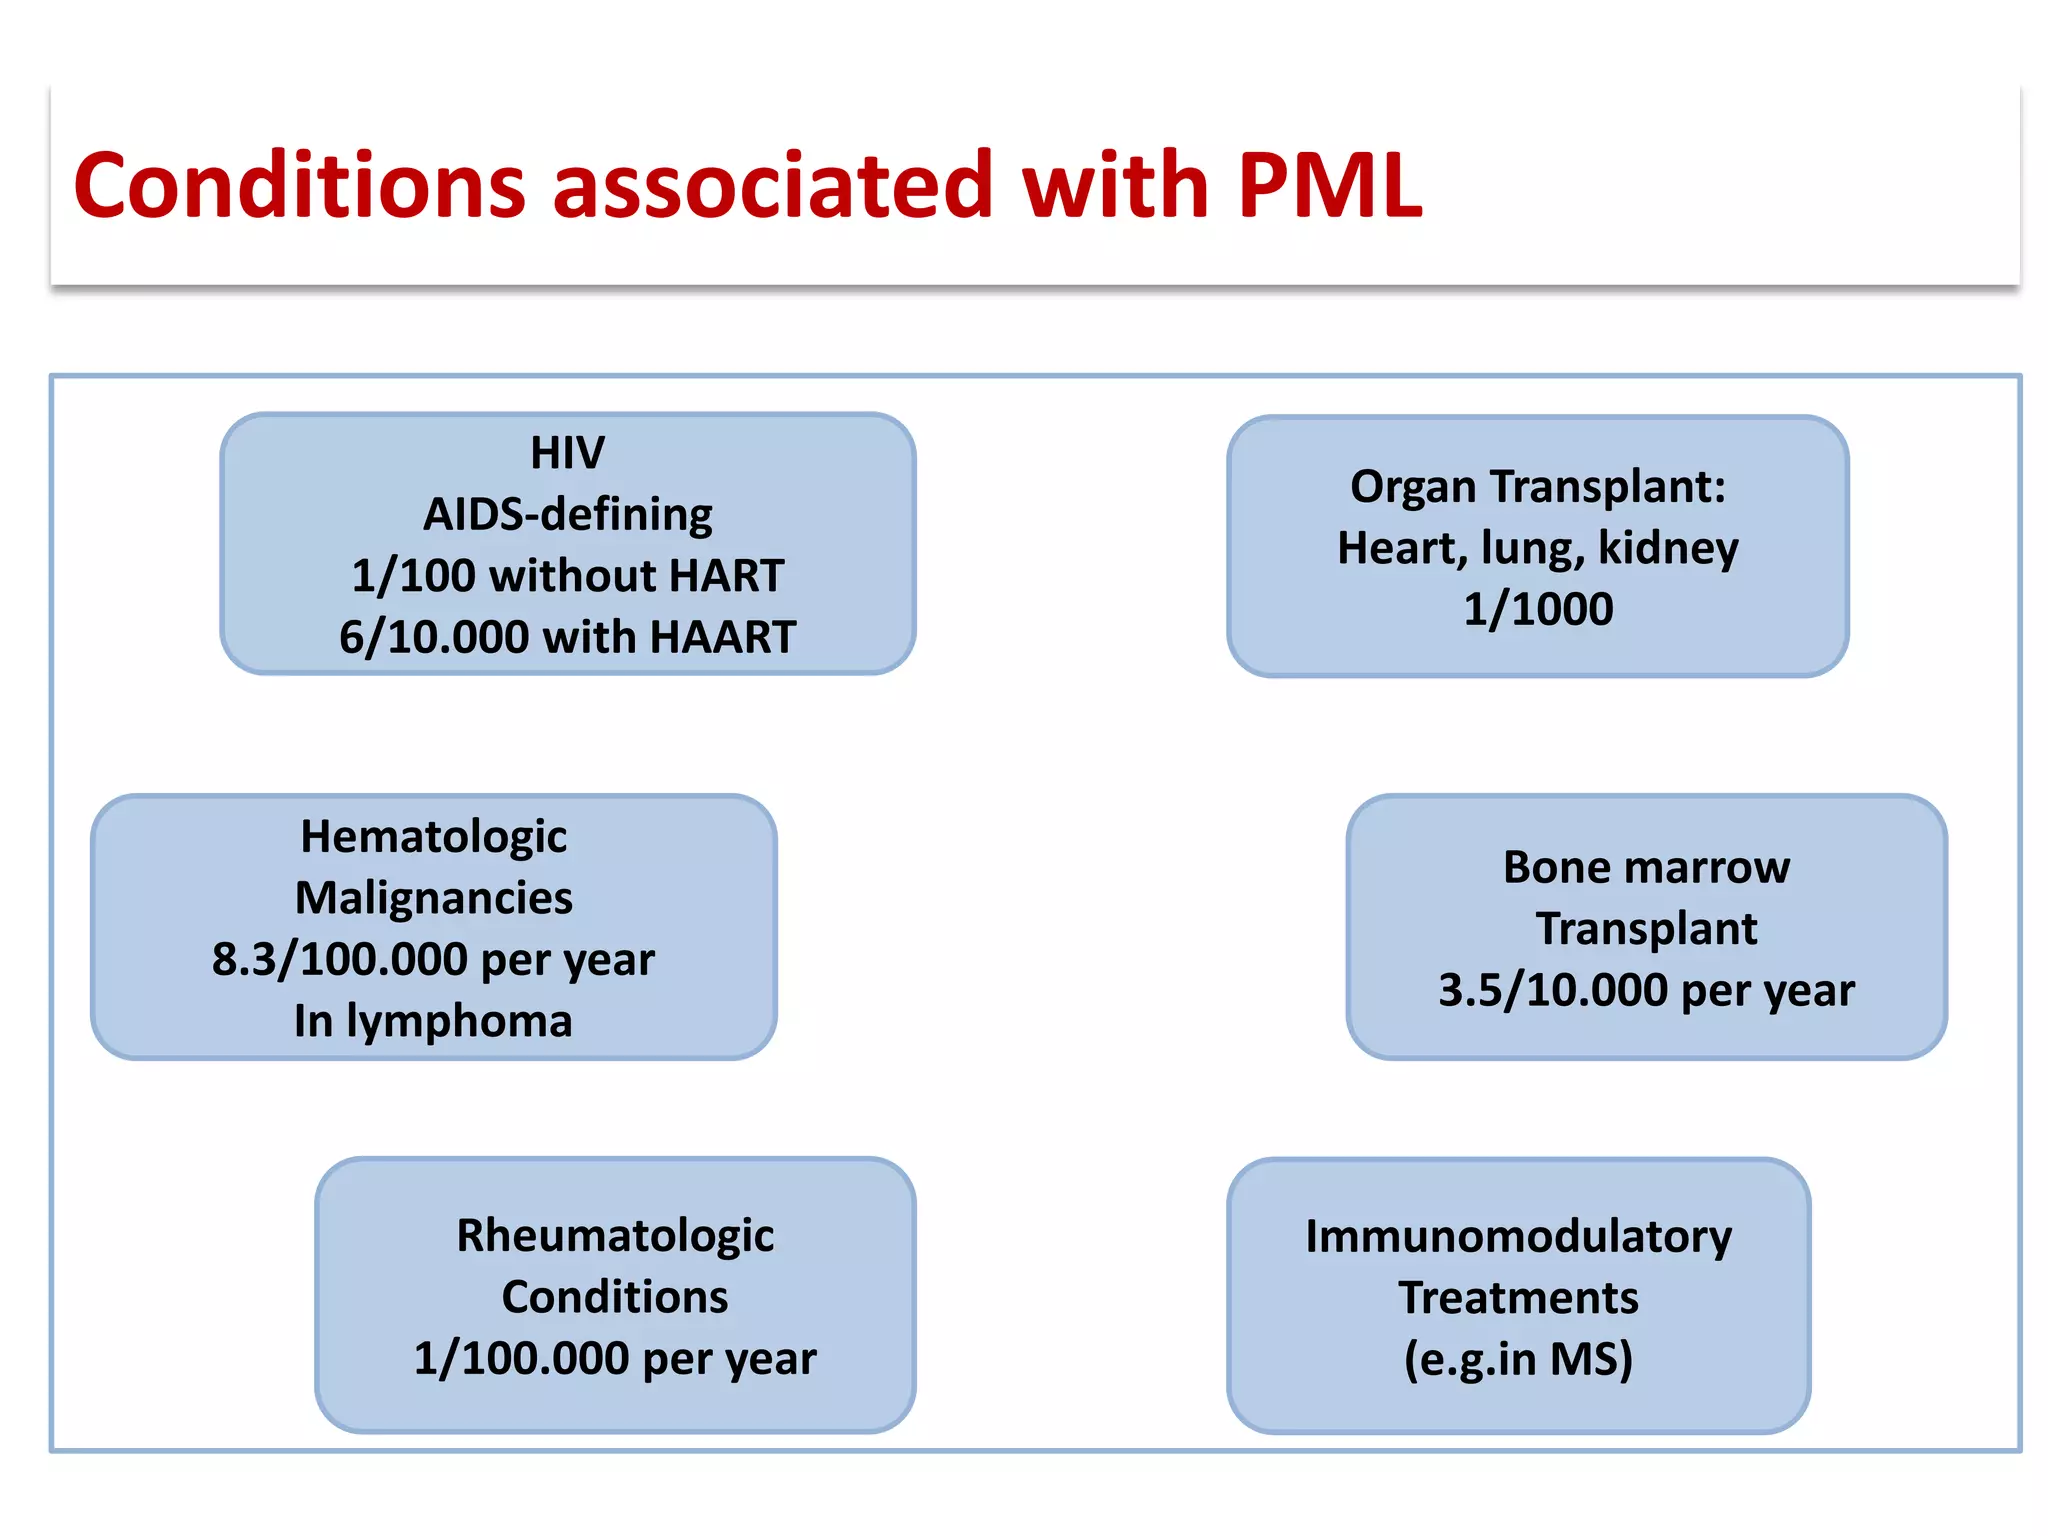

This document discusses progressive multifocal leukoencephalopathy (PML), an opportunistic infection caused by the John Cunningham virus (JCV) that leads to demyelination in the central nervous system. It highlights the epidemiology, clinical manifestations, diagnostic methods, and risk factors associated with PML, particularly in immunocompromised patients and those undergoing immunomodulatory therapies. It also presents data on the incidence of PML in patients treated with natalizumab and other therapies, addressing the relationships between these treatments and the development of PML.